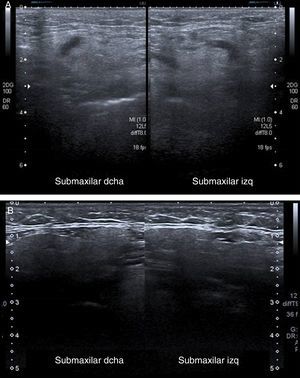

Varón de 63 años de edad, con leucemia mieloide aguda, hospitalizado para realización de trasplante de médula ósea. El paciente comenzó de manera súbita con un aumento de tamaño de la región cervical y submandibular, y se sospechó un síndrome linfoproliferativo postrasplante con aparición de adenopatías cervicales. Al paciente se le había realizado en las 48 horas previas una TC craneal, administrándole 80ml de contraste yodado intravenoso (Iohexol 300 mgI/ml, Omnipaque®, GE Healthcare Ireland, IDA Business Park Carrigtohill Co. Cork, Ireland). La función renal había empeorado durante el ingreso, presentando una creatinina de 1,4mg/dl en el momento del cuadro clínico. Se realizó una ecografía cervical en la que únicamente se observó un aumento de tamaño de ambas glándulas submaxilares, que presentaban un aspecto edematoso con pérdida de la diferenciación de su contorno (fig. 2 A). La ausencia de adenopatías, la bilateralidad del proceso y el antecedente de exposición reciente a contraste yodado orientaron hacia una posible reacción adversa. Se pautaron corticoides y se produjo una resolución completa del cuadro clínico en 48 horas, con confirmación ecográfica (fig. 2 B).

A) Imagen de ecografía cervical con sonda lineal en la que se observa un aumento difuso del tamaño de ambas glándulas submaxilares, que presentan un aspecto edematoso con pérdida de la diferenciación del contorno glandular. B) Ecografía cervical realizada a las 48 horas en la que se observa una adecuada diferenciación del parénquima glandular con desaparición de los signos inflamatorios.